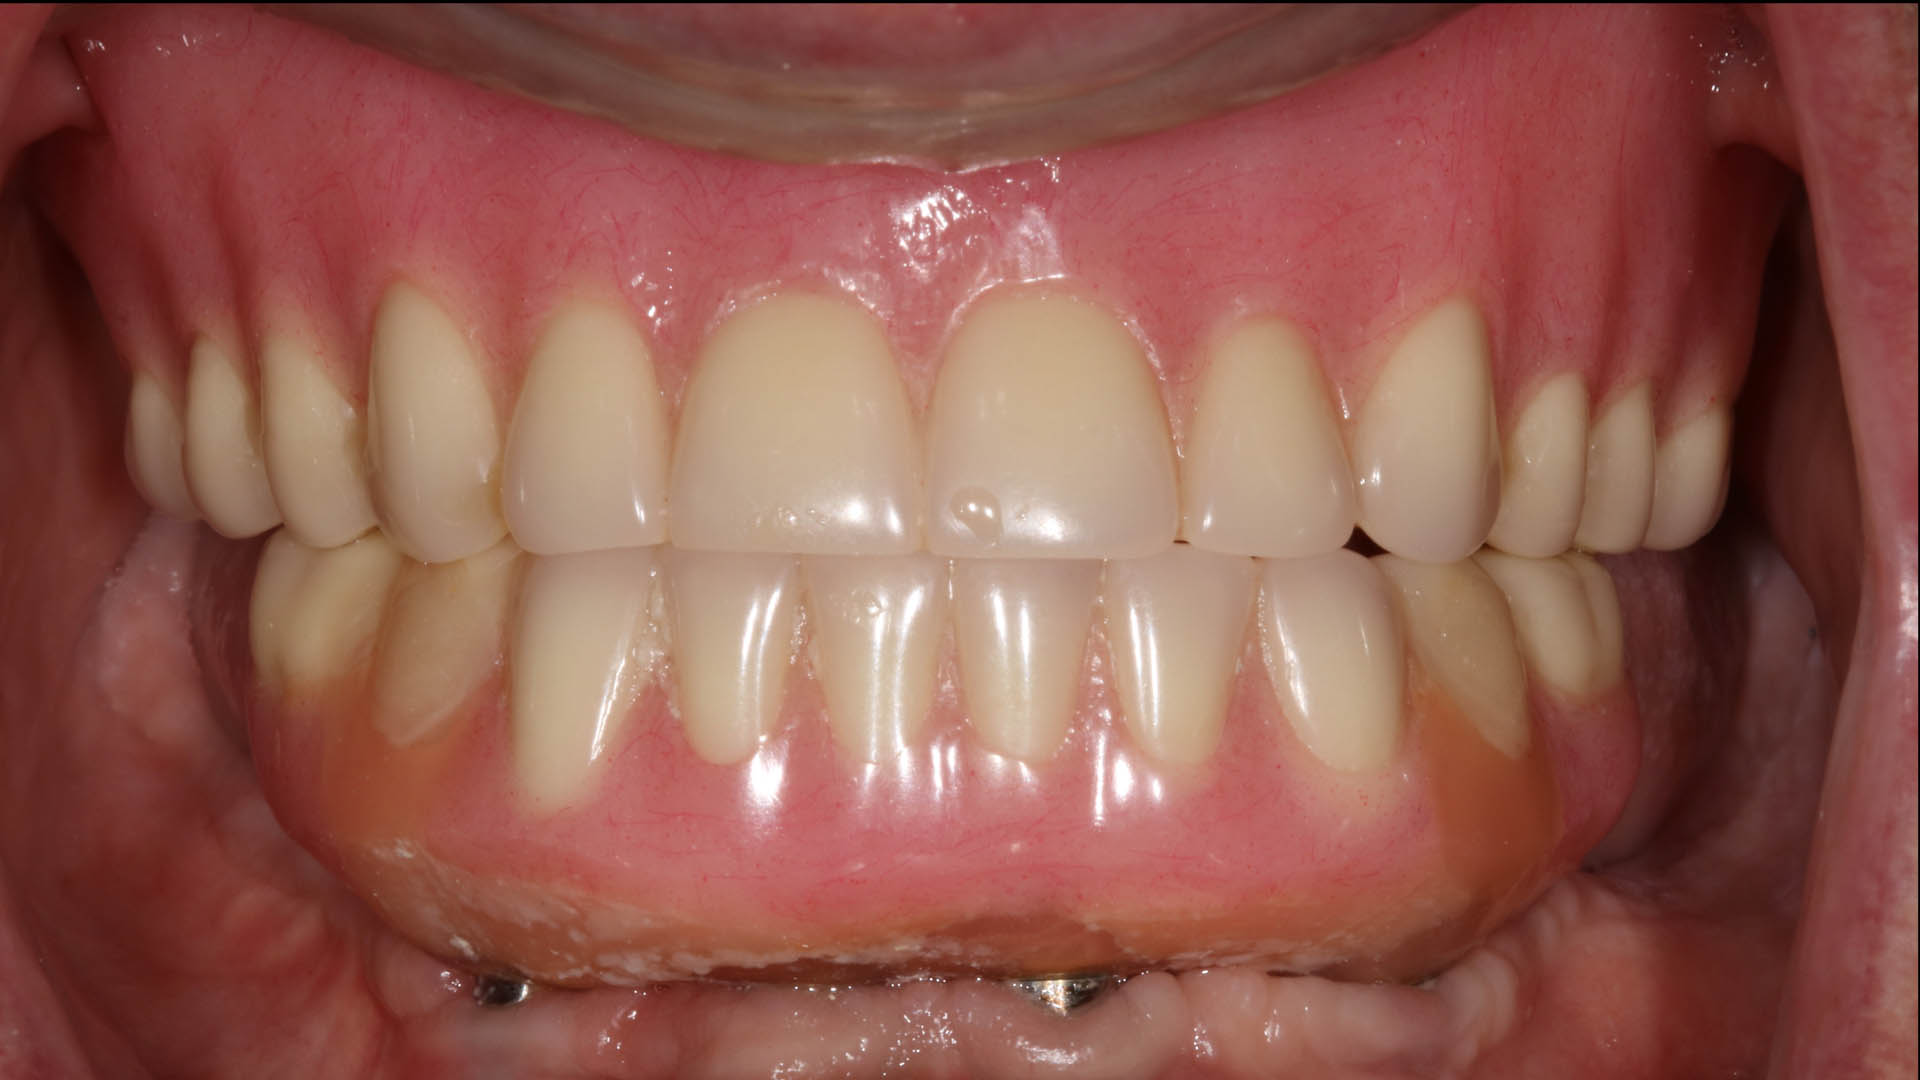

Take a glimpse into the magic of Coral Gables Dentistry through our before and after pictures. See firsthand the incredible smile makeover transformations that have brought confidence and joy to our patients.